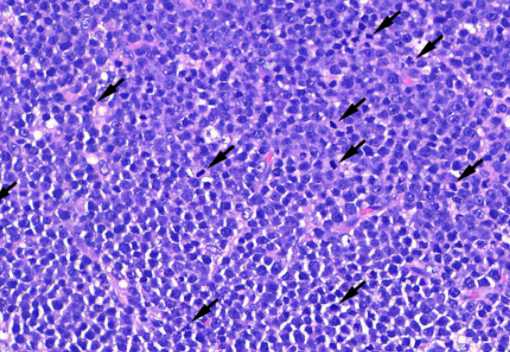

貓 淋巴癌 胸水 胸腔前縱膈腔腫瘤 腹腔淋巴結腫大 化療 不是感冒 首頁 病例分享 腫瘤科 貓 淋巴癌 胸水 胸腔前縱膈腔腫瘤 腹腔淋巴結腫大 化療 不是感冒 1歲已絕育母貓,就診前一周精神食慾下降、咳嗽,在他院診斷感冒治療無效而就醫。 經急診醫師檢查發現有嚴重胸水、前縱膈團塊、腹腔淋巴結腫大。 排除心臟病、白血病等等鑑別診斷後採樣確診為貓咪的淋巴癌。 雖然淋巴癌的治癒率非常低,但對化療有良好反應的機率很高,於是後續開始化療計畫。 影像檢查結果 嚴重胸水 抽完胸水後發現前縱膈腔團塊. 腹腔內淋巴結多發腫大 病理切片: 箭頭所指處為有絲分裂中的淋巴癌細胞